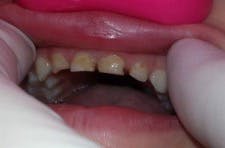

A strip crown technique (in this case, Activa BioActive-Restorative) requires fewer steps, takes less time, offers a better seal against secondary caries, and provides a more durable and fracture-resistant restoration. First, I trim and prefit Nowak strip crowns so they are even with the sulcus (figure 2). Because the prep in these cases is usually quite minimal, I typically do not need local anesthetic.

I prep the teeth with a No. 4 or No. 6 round bur, slowly removing decay with short, light touches. Incisal reduction is usually unnecessary, and I avoid it whenever possible. If needed, I use a very fine diamond to refine, shape, and open contacts. I only work two to three seconds at a time and keep a 2×2 gauze under the teeth for children who are uncomfortable with the water spray and suction. Figure 3 shows the final prep.